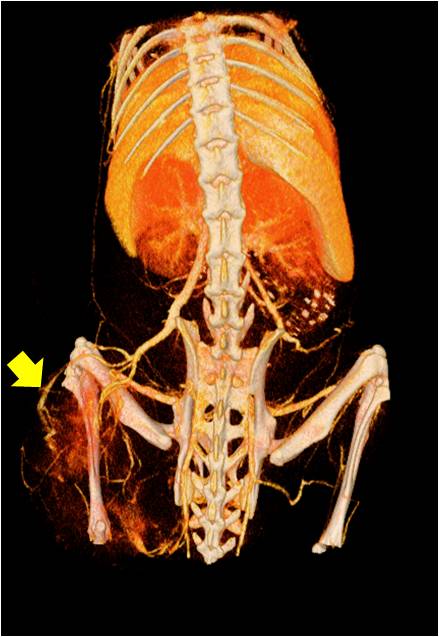

能進行全身血管成像研究,獲得高分辨率的血管造影影像;

心血管

胸部和心血管的層析成像 胸部和心血管的3D圖像